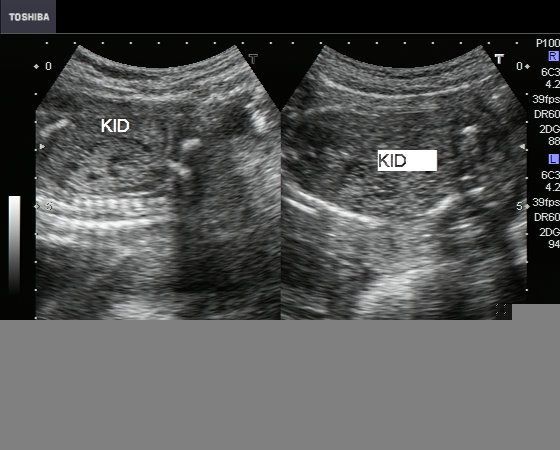

Sonography of the fetal abdomen in this 2nd trimester fetus reveals- 1) bilateral grossly enlarged fetal kidneys, almost filling the entire abdomen 2) markedly hyperechoic fetal kidneys with minute anechoic areas within them.        3) oligohydramnios 4) poorly distended urinary bladder. This ultrasound image is diagnostic of fetal autosomal recessive polycystic kidney disease (ARPKD). This image was taken by Dr. Durr-e-Sabih, Pakistan, using a Toshiba Nemio-30 color doppler machine.

These ultrasound images (another case) also show grossly enlarged, echogenic fetal kidneys with minute cystic lesions (1 to 2 mm.) within them. The cystic lesions in this case, as well as the previous case show a typical rosette like pattern that is typical of autosomal recessive polycystic kidney disease. These ultrasound images are courtesy of Dr. Jaydeep Gandhi, Mumbai India. The machine used is  a Nemio 30 from Toshiba.